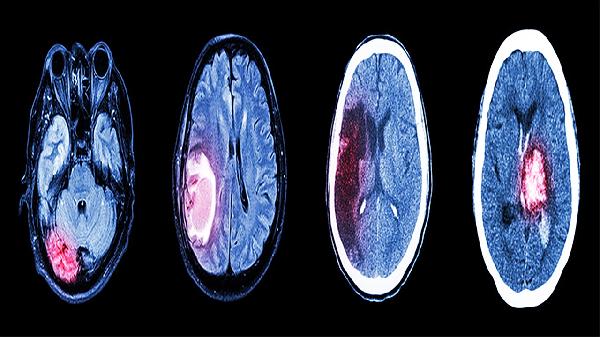

药物中的有效成分能减轻脑细胞缺氧损伤,对脑动脉硬化、脑供血不足导致的记忆力减退、注意力不集中有改善作用。在脑梗死后康复期使用可帮助神经功能恢复。